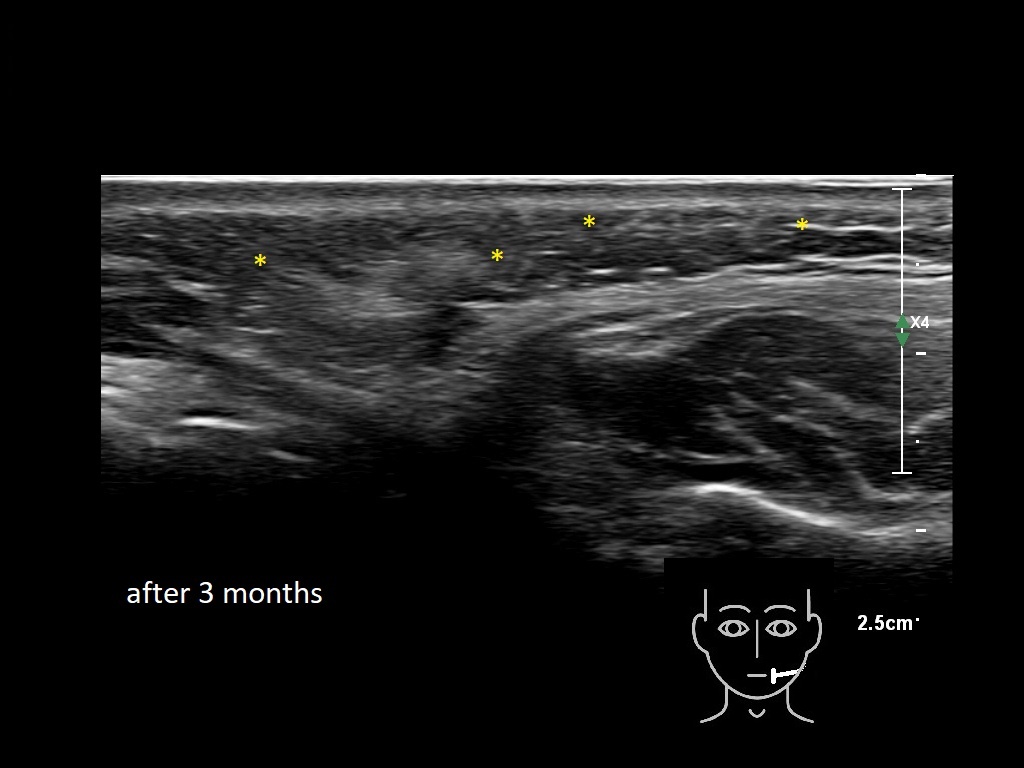

Draw in the image on the right where the fillers are located. To check if your answer is correct, please click on the secondary image.